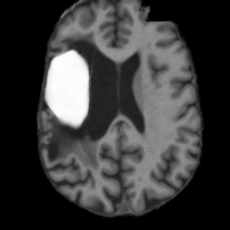

(a)PathologicalInput ImageSynthSR [18]Brain-ID [28]UNA [30]USBHealthyGround TruthRefer to captionRefer to captionRefer to captionRefer to captionRefer to captionRefer to captionRefer to captionRefer to captionRefer to captionRefer to captionRefer to captionRefer to captionRefer to captionRefer to captionRefer to captionRefer to captionRefer to captionRefer to captionRefer to captionRefer to captionRefer to captionRefer to captionRefer to captionRefer to caption(b)HealthyInput ImageConditionalLesion MaskUNA [30]USBRefer to captionRefer to captionRefer to captionRefer to captionRefer to captionRefer to captionRefer to captionRefer to captionRefer to captionRefer to captionRefer to captionRefer to captionRefer to captionRefer to captionRefer to captionRefer to caption

Figure 5: Comparison of bidirectional brain editing. (a) pathology-to-healthy, the circles and arrows highlight lesion regions and unsuccessful reconstructions; (b) healthy-to-pathology. Note that SynthSR and Brain-ID cannot perform healthy-to-pathology editing.

Pathology-to-Healthy Editing. Fig. 5 (a) presents comparison results on four input brain images with lesions of varying sizes, shapes, and densities. All competing models, although specialized for healthy brain image synthesis, struggle to reconstruct pathological regions, especially near lesion boundaries. In contrast, USB accurately reconstructs the corresponding healthy brain, even in challenging cases with large, high-density lesions where normal brain structures are almost completely obscured (last row). Tab. 2 provides a quantitative comparison for pathology-to-healthy editing, where USB achieves the best performance across all three datasets, demonstrating the effectiveness of its unified framework in reconstructing healthy brains from pathological inputs. Additional results are in Suppl. B.

Healthy-to-Pathology Editing. As shown in Fig. 5 (b), given a healthy brain image paired with a random lesion mask, USB seamlessly embeds the lesion into the healthy anatomy, producing realistic pathological appearances consistent with surrounding structural context. Yet UNA’s syntheses are visually unrealistic, with the conditioned lesion mask simply overlaid as a parallel layer onto the healthy brain. Tab. 3 further demonstrates USB’s superior performance. The evaluation was conducted on 100 pairs of lesion masks and healthy brains, with real stroke images